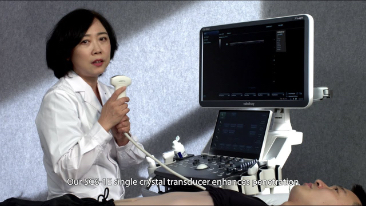

Algemene beeldvorming

Mindray Resona-oplossingen voor algemene beeldvorming helpen clinici bij het realiseren van nauwkeurigere en effici?ntere diagnose- en behandelingsresultaten door middel van sondes voor aparte toepassingen en effici?nte klinische toepassingstools.